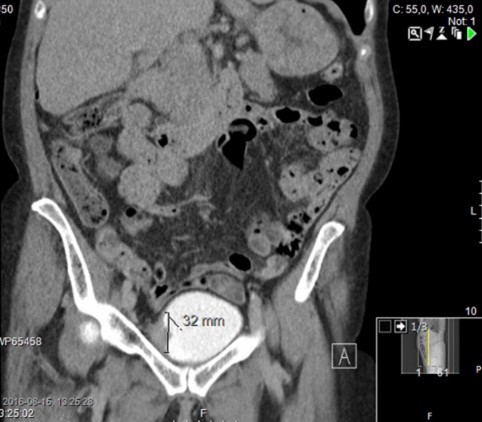

• Bukaortaaneurysm med stort vänstersidigt hematom och pågående blödning retroperitonalt.

Förmodad urinblåsetumör